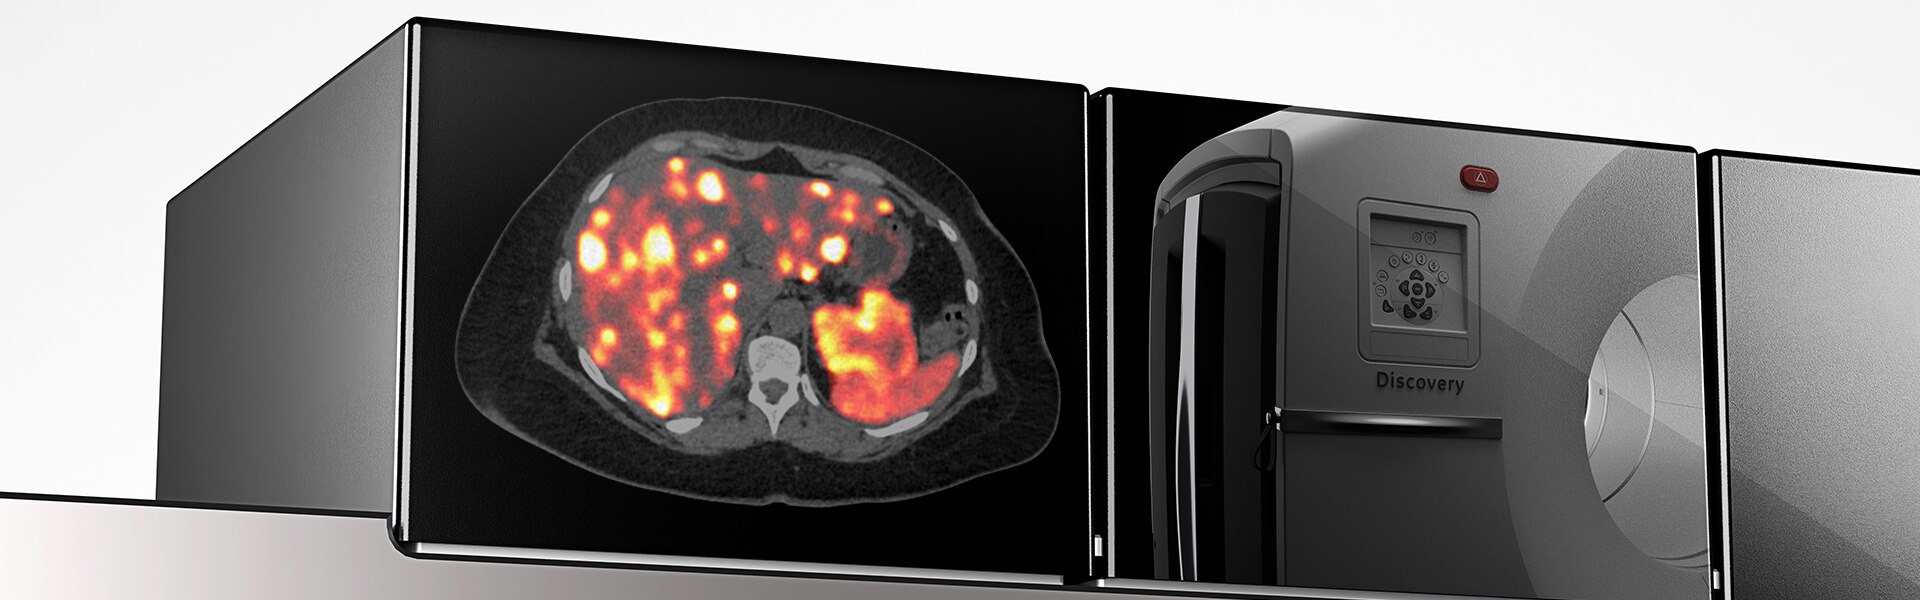

Présentation du système Discovery MI Gen 2

La détection numérique revisitée

Discovery MI Gen 2 a été conçu pour accroître votre productivité

- Un champ d’exploration extensible

- Un pic NECR4 amélioré de 50%

- Sensibilité exceptionnelle par cm (cps/kBq/cm)

- Durée d’acquisition réduite de 33 %4

- Dose injectée réduite de 33 %4

Nouvelle génération de TEP numérique